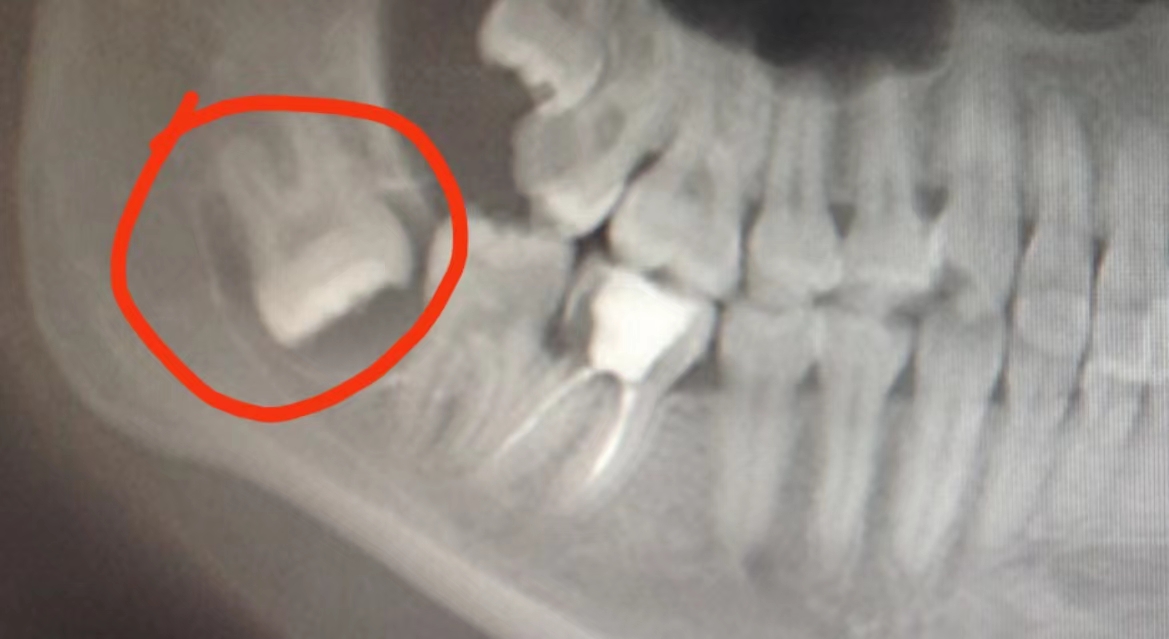

深埋阻生牙x光片

颌骨里为何藏着有牙齿?依沙克江告诉记者,不少复杂阻生牙深藏在颌骨里,由于被骨组织包裹,无法正常向上萌出,便横向生长。有的就会形成颌骨囊肿,引发各种牙齿健康问题,有的甚至会挤破临牙,造成更严重口腔问题。这种深埋复杂阻生牙,不通过医学检查发现不了,所以很多人并不知道自己颌骨里还藏着牙齿。